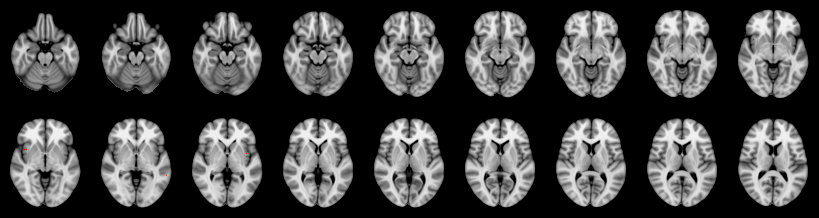

Combined

Tippett:

Fisher:

Stouffer:

Edgington:

Mudholkar–George:

Friston:

IUT/Conjunction/Nichols:

Hotelling T2: